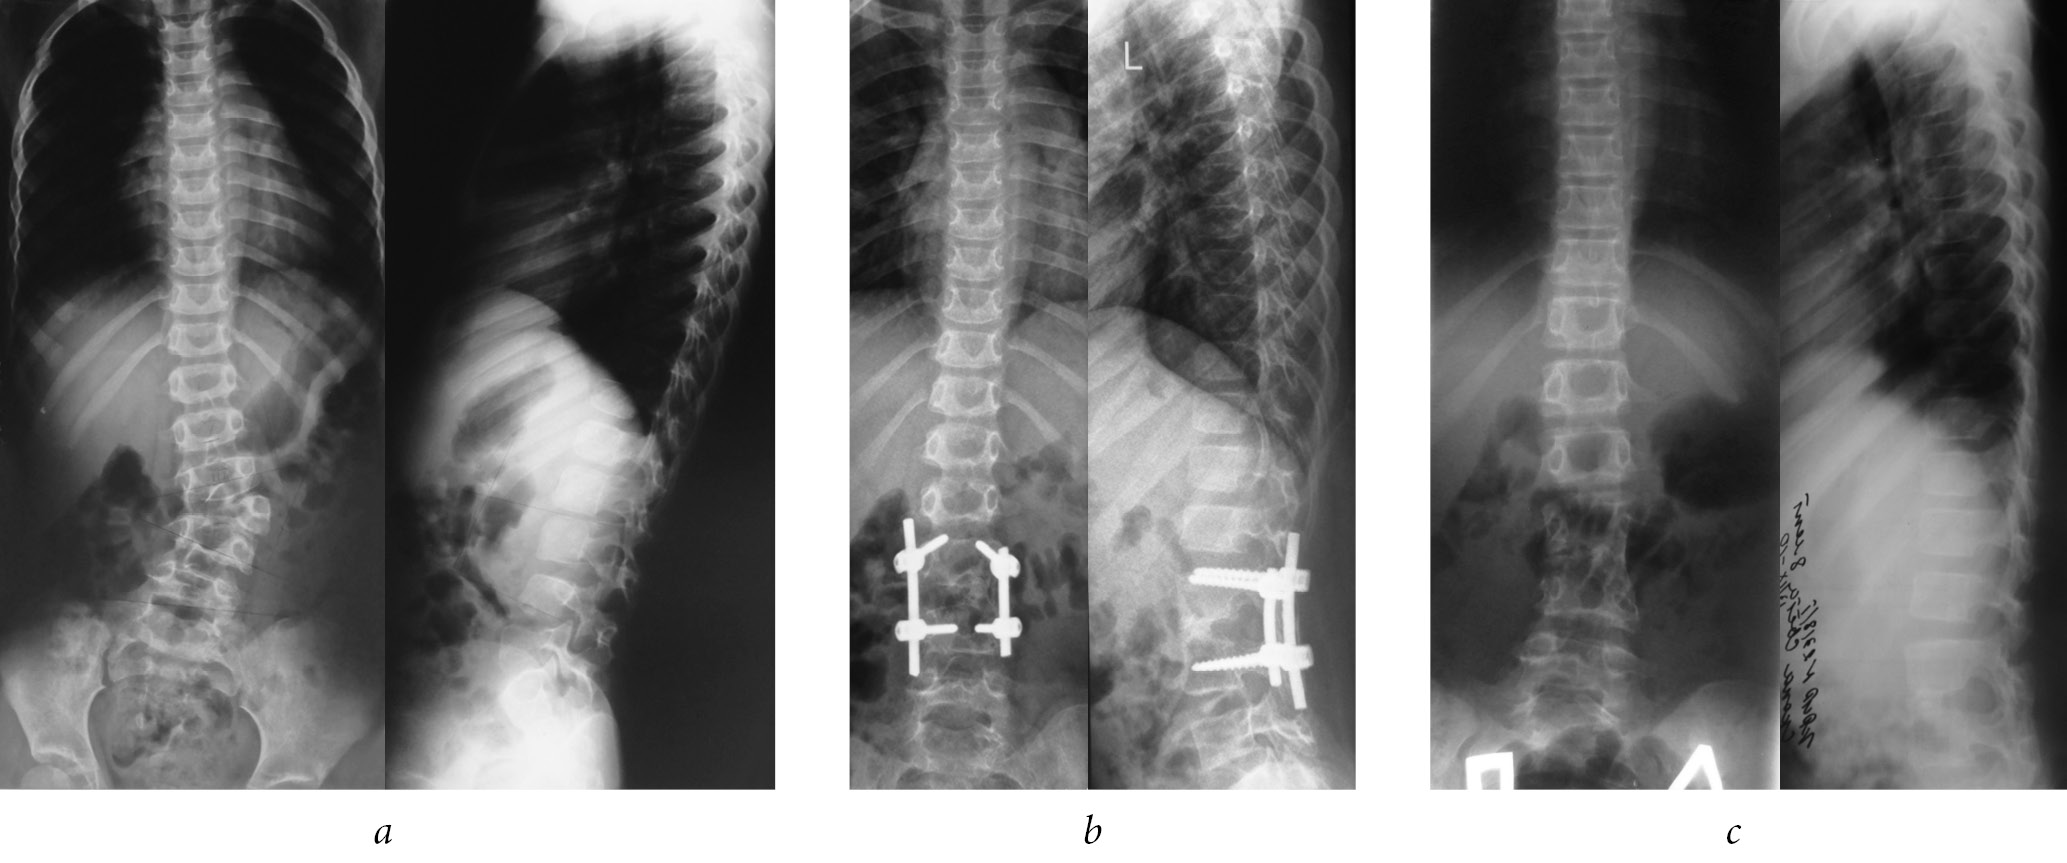

After surgery in patients of both groups, a radical correction of both the scoliotic and kyphotic components of the deformity was achieved with the restoration of physiological profiles of the spine. The insignificant residual value of the deformity, as well as the difference in the measurement of correction indicators between the groups and in the long-term follow-up period, corresponded to the values of the measurement error. As a result of the surgery, it was possible to restore the sagittal profile of the deformed spinal motion segment (Figure).

Radiographs of patient K., 1 year and 3 months, with congenital kyphoscoliosis with posterolateral semivertebra: (a) before surgery, the scoliosis angle is 26°, and the kyphosis angle is 12°; (b) 1.5 years after the surgery from a combined approach; and (c) 6 years after removal of surgical hardware

However, in the long-term period after surgery, a progression of the kyphotic component of the deformity in the lumbar spine from –19° to –8° (p = 0.04) was noted in the group of patients operated only from the dorsal access, while the correction value of the scoliotic component of the curvature remained stable throughout the entire period. At the same time, it should be noted that the achieved correction of deformity after surgery remained stable during the long-term follow-up period in patients using a combined approach. During the surgery, correction was achieved by stabilizing a larger number of vertebrae in Group 1 compared with that in the comparison group. This result was because dorsal access did not provide a sufficiently good and complete visual view and achieve full mobility in the intervention zone. The results are presented in Table 4.